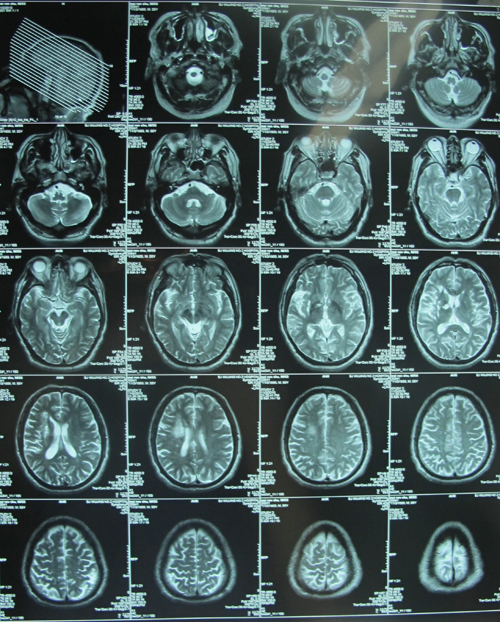

头颅MR平扫:右侧半卵圆中心、基底节区梗塞灶(亚急性、慢性);左侧半卵圆中心、基底节区散在腔隙灶;右侧颈内动脉海绵窦段管径较对侧纤细;双侧上颌窦炎症。并左侧上颌窦内粘液囊肿。